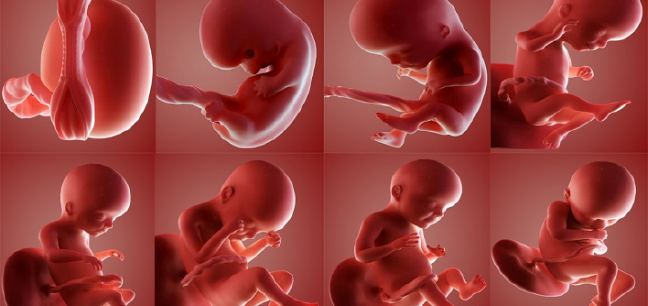

Bebeğimin Cinsiyeti Ne Olacak

Bebeğimin Cinsiyeti Ne Olacak.